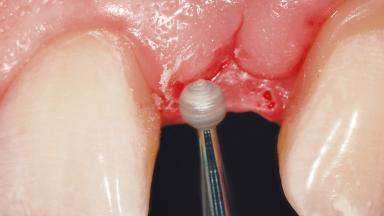

Early Implant Placement in a Maxillary Lateral Incisor Site

In the fall of 2003, a female patient was referred to the School of Dental Medicine, University of Geneva, for treatment of a traumatic fracture of a maxillary left lateral incisor. While at home, the patient fell down and hit a heating radiator with the anterior maxilla. During the initial examination, a week after the accident, the patient was in good general health condition and signs of pain/discomfort or clinical/radiographic infection were not observed. A moderate and localized hematoma with associated swelling persisted on the left side of the upper lip. Clinical assessment revealed a horizontal fracture at the cervical third of the anatomic crown of the maxillary left lateral incisor. In addition, a vertical crack line projecting into the cementoenamel junction (CEJ) called for a comprehensive assessment of the tooth restorability options.